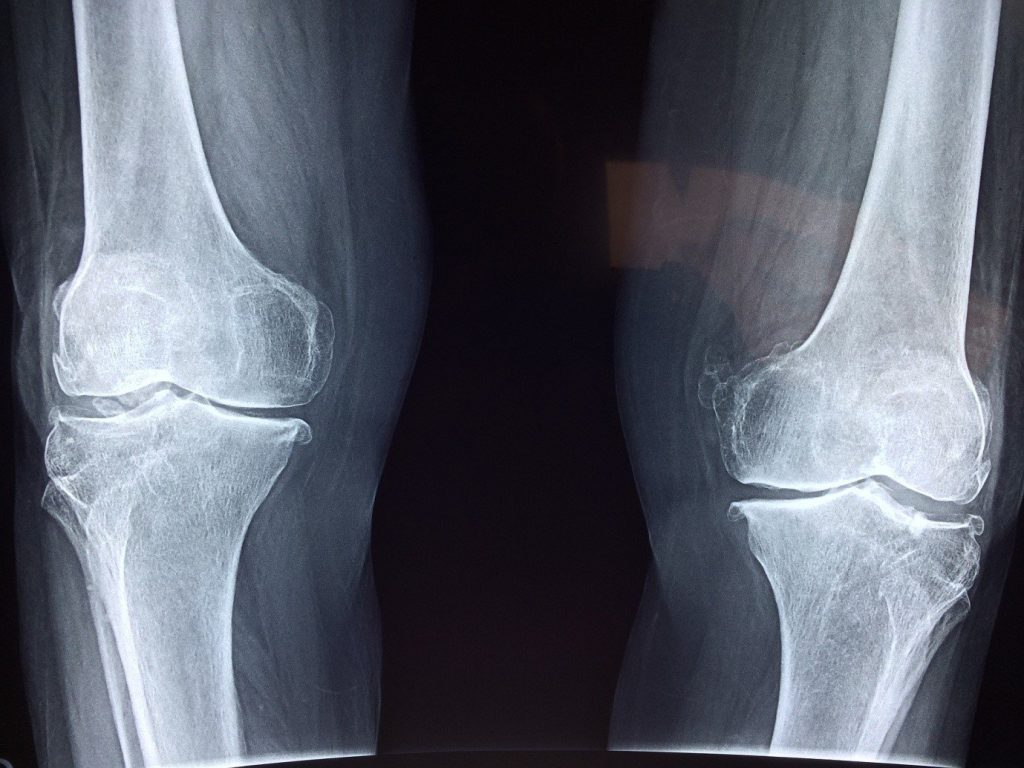

If you’ve suffered a traumatic injury or if a tear is suspected, your physio may refer you for an x-ray or MRI may be ordered.